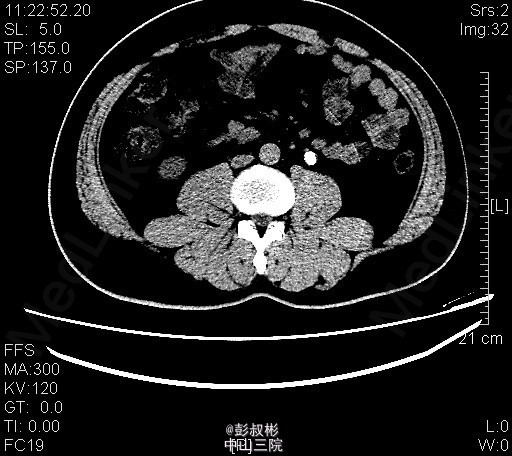

1、体检发现左输尿管结石2月 2、患者2月前体检发现左输尿管结石,无腰痛,无其他部位反射痛,无发热,无恶心,当时未给予治疗。今为求进一步治疗来我科住院,起病以来患者一般情况尚可,体重无下降。

3、查体:双肾区无红肿、隆起,左肾区叩击痛(-),右肾区叩击痛(-),左侧肋脊点、肋腰点压痛(-),右侧肋脊点、肋腰点压痛(-)。腹平软,左侧输尿管走行区压痛(-),右侧输尿管走行区压痛(-),膀胱区无膨隆,压痛阴性 4、辅助检查: 我院 腹部平片 左输尿管上段结石 ;泌尿系b超 前列腺增大;右肾多发结石;左肾形态失常;左输尿管上段结石并左肾积液。CT示左输尿管上段结石、左肾小结石

5、诊断:左输尿管上段结石并左肾积液 6、入院后予以完善术前检查,未见明显手术禁忌,在全麻下行“单孔腹腔镜下左输尿管切开取石术”,术后予以一级护理,心电监护,低流量吸氧,营养支持,抗炎对症治疗。术后注意观察事项:保持引流管及尿管通畅,留意尿量及引流量